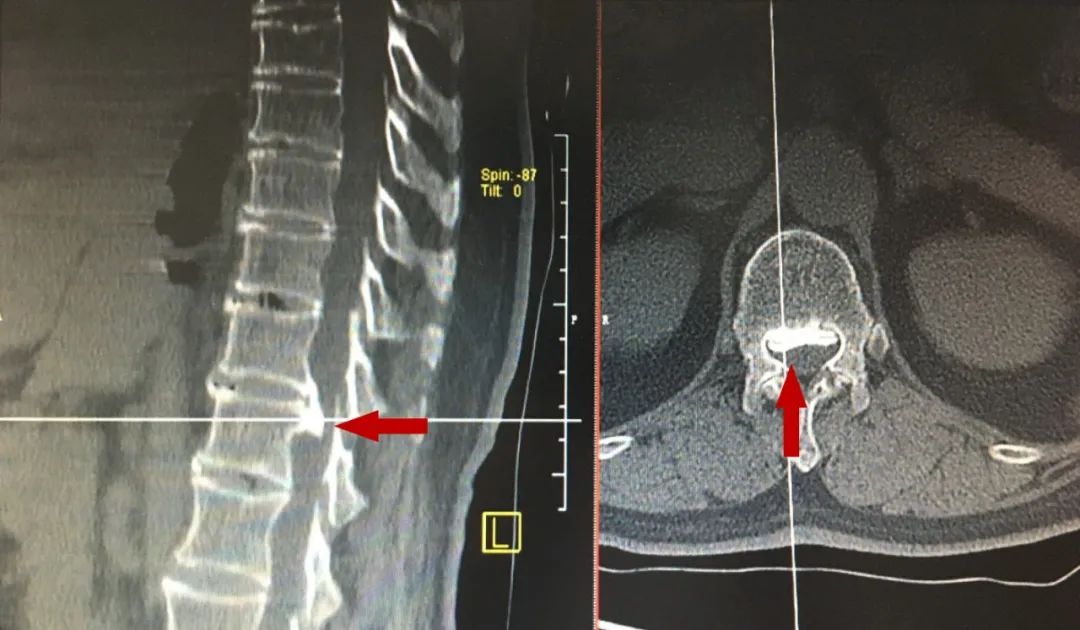

▲脊柱CT(红色箭头指示骨化块)